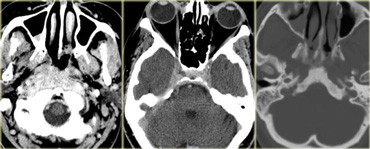

Cystic versus Solid

There are many cystic lesions that can simulate a CNS tumor.

These include epidermoid, dermoid, arachnoid, neuroenteric and neuroglial cysts.

On the far left a craniopharyngioma with an enhancing rim surrounding the cystic component.

In the middle a neuroenteric cyst with the contents of which have the same signal intensity as CSF.

On the right a glioblastoma multiforme (GBM) with a central cystic component.

The enhancement in GBM is usually more irregular.